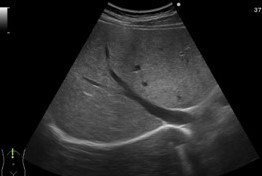

超音波検査

肝臓/胆のう/膵臓などを痛み無く検査ができます。蠕動や血流の異常など症状に合わせて、検査と評価を行います。